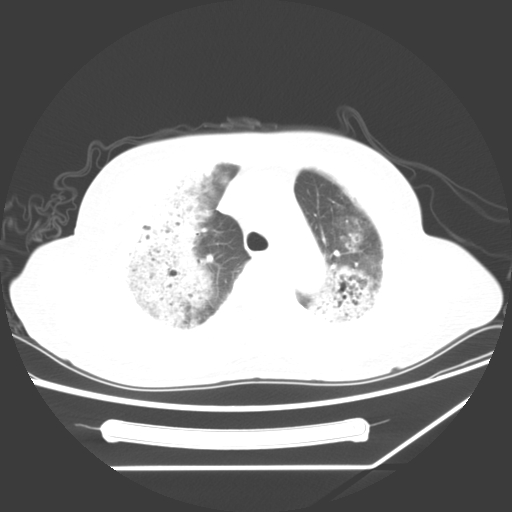

标题: CT25393:病人45岁,咳嗽,吐黄痰带血丝,发热,胸闷月余 [打印本页]

标题: CT25393:病人45岁,咳嗽,吐黄痰带血丝,发热,胸闷月余

1、左肺中央型肺癌并双肺弥漫性转移   2、双肺部感染    3、肺大泡     4、左侧胸腔积液

双侧肺弥漫性病变,可见“空泡征”及“蜂窝征”,考虑肺泡癌可能性大,左侧胸腔积液,考虑胸膜受累可能!

1)不排除肺泡癌可能。2)左侧胸腔积液。